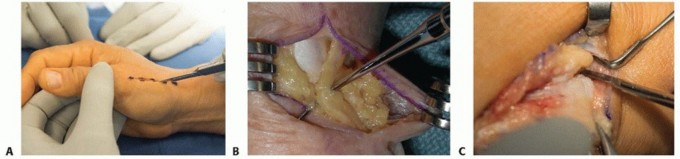

TECH FIG 1 • A. Dorsal longitudinal incision along the ulnar aspect of the first dorsal compartment. B. Surgical incision with identification of the radial sensory nerve. C. Dorsal branch of radial artery is mobilized and protected by retracting it dorsally and proximally. The first dorsal compartment is released.Identify the dorsal branch of the radial artery deep to the abductor pollicis longus and extensor pollicis brevis tendons running in a dorsal and ulnar direction. Carefully mobilize and protect it by retracting it dorsally throughout the remainder of the case (TECH FIG 1C). The radial artery courses directly over the STT joint.Identify the base of the thumb metacarpal, and complete a longitudinal capsulotomy to expose the base of the metacarpal, the entire trapezium, and the distal aspect of the scaphoid.Fluoroscopy is used to confirm the location of the CMC joint if necessary.